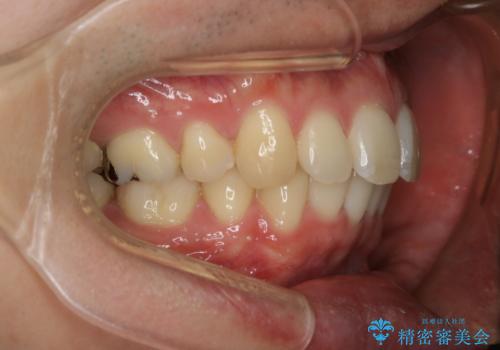

がたつき、口ゴボ(出っ歯)、真ん中のずれを抜歯矯正治療で治す。ワイヤー矯正治療

もともとの歯の根っこの位置の関係で、治療途中において上下の真ん中の位置がずれてしまいました。機能的には問題ありませんが患者様と相談し、期間を延ばした上で真ん中を合わせる治療を追加で行いました。